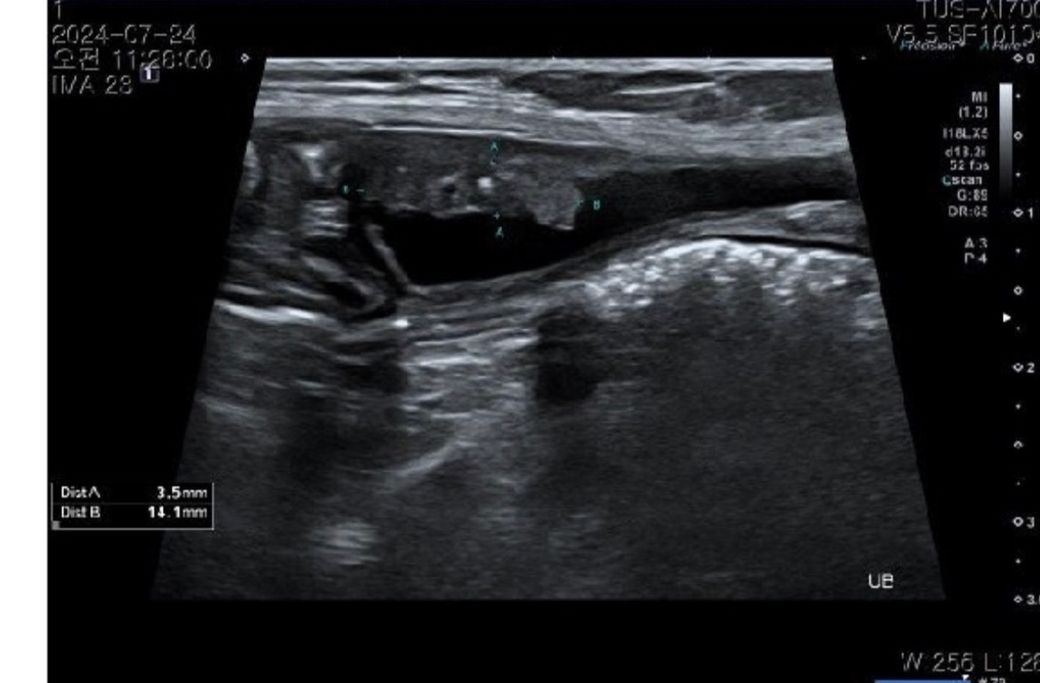

방광 종양 초음파 전,후 설명 부탁드리겠습니다ㅠ

후(조직검사 떼고나서 찍은거 같습니다?)

전 ct

초음파 검사는 다른 영상검사와 다르게 정지화상으로 얻을 수 있는 데이터는 적고, 임상적 의미도 거의 없습니다.

검사를 하는 과정에서의 동시성이 무엇보다 중요합니다. 즉, 검사를 한 초음파 검사자의 소견이 가장 중요한요소로 정지화상만으로 평가하는것은 오만에 가까운 위험한 행동입니다.